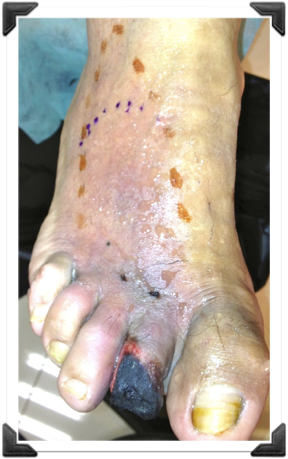

Sindrome Neuroisquemico

Nunca Cirugia

Hasta Tener Flujo

Amputación del 2do dedo Mal Indicada

Dr. Luis Villanueva